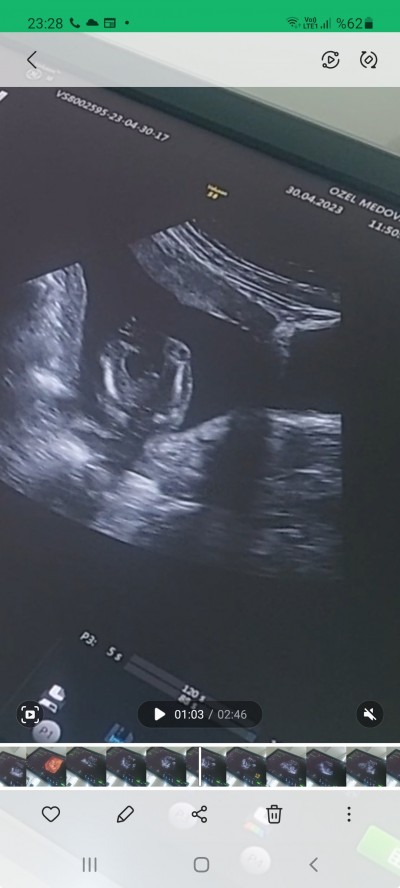

16+5 haftalik hamileyim özele gidiyorum basindan beri 12. Haftada doktorum pipi cikintisi var %80 erkek dedi geceb hafta gittim %100 prenses dedi kafam karisti buda iki bacagi sizce ne bebegin cinsiyeti ?

Yorumunuza bakmadan erkek olduğunu gördüm ultrasona bakarak şimdi şöyle bir durum var normalde burda bebeğin komple ultrason görüntüsünü paylaşıp cinsiyet soruyorlar çok saçma geliyor fakat sizin ultrasonunuz sagdece orasını gösteriyor kızlarda uctane çizgi oluyor erkeklerde ise bu şekilde fakat tabiki bu yorumu yapmak bize düşmez detaylı ultrasonunu bekleyip doktorunuzdan öğrenmeniz en sağlıklısı olur sonuçta bizlerde doktor değiliz ki doktorlar bile yaniliyor

Kiz   kesin  canim   benim  12  de  net   pili  gorduk  gecen   plesenta yi  pipi  sanmiatir  suan  3  cizgi  var   kiz  yani

Canım 100 / 100  erkek çunku benim oğlumun ultrasyon resmide aynı böyle :P<3 :)

Kız bnce kizlarin özel bölgesi dolgun olurmus:) sağlıcakla gelsin :))